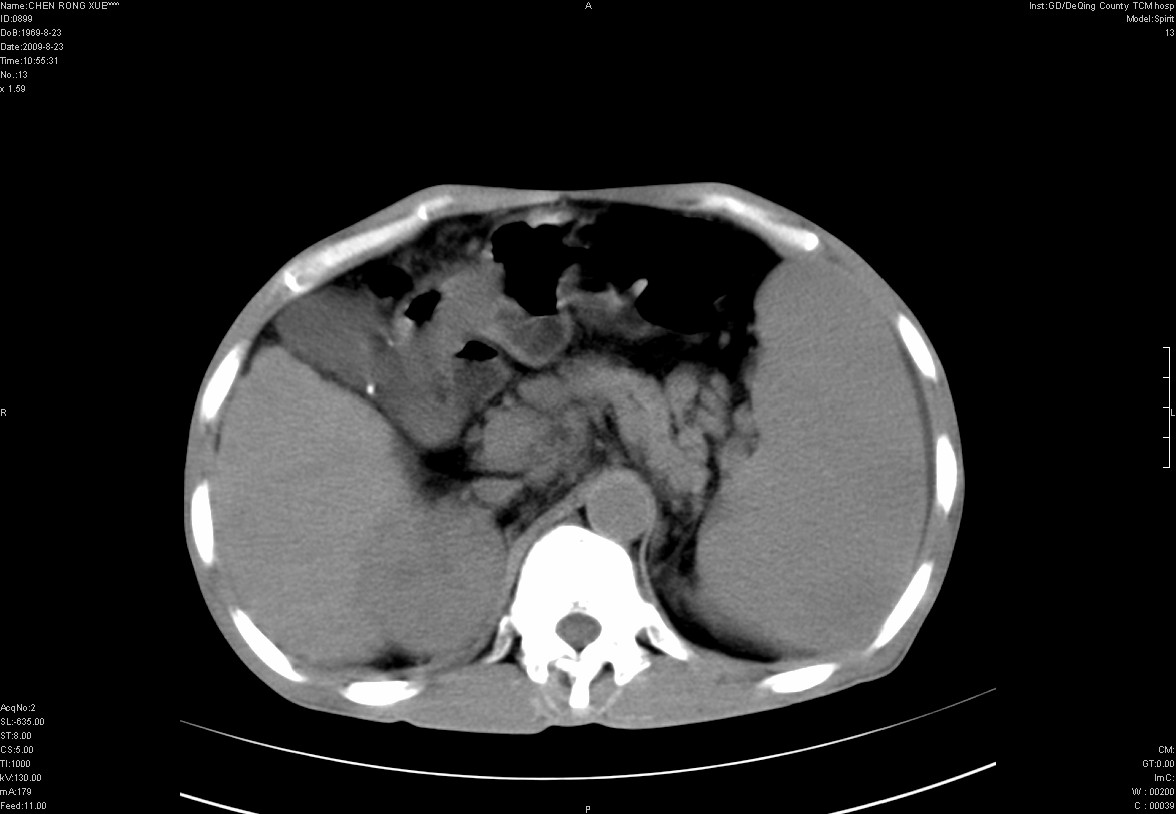

以下是引用zxl51642在2009-8-23 12:56:00的发言:[br]1、肝硬化、脾大;2、慢性胆囊炎;3、右肾占位并右侧腰大肌受侵,考虑恶性可能性大,建议增强扫描进一步检查。

以下是引用qiuleiyu在2009-8-23 15:17:00的发言:[br]1、慢性肝病,肝硬化,脾大,门脉高压。胆囊小结石。[br]2、右肾明显肿大,伴片状低密度灶,累及右侧腰大肌,肿瘤及炎症性病变皆有可能大,建议增强。

以下是引用zjzjr在2009-8-23 17:42:00的发言:[br]1、慢性肝病,肝硬化,脾大,门脉高压。胆囊小结石。[br]右肾脓肿波及肾周,建议增强